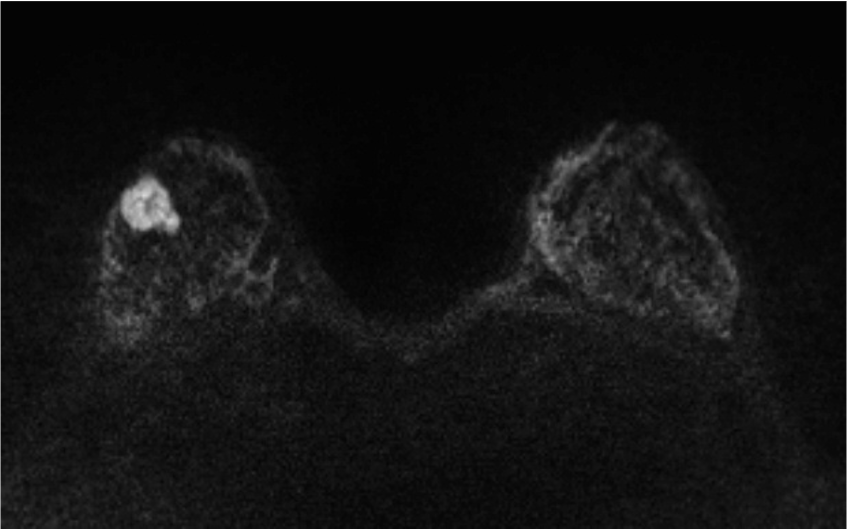

5. Ultrafast DCE

乳癌の病変は、超早期(10相目: 造影剤注入32.5秒後)から急速に造影されている。背景乳腺は超早期では、ほとんど造影されていないが、17相目では軽度増強されている。